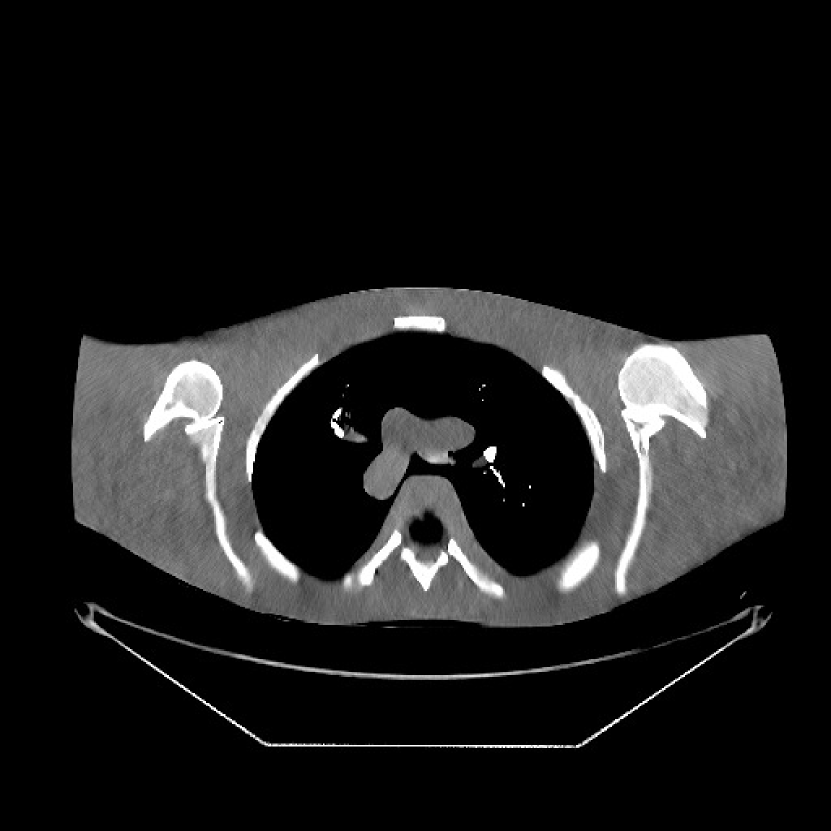

We used the pre-learned union of 15 square transforms from the XCAT phantom simulations to reconstruct the synthesized helical chest scan volume of size with mm and mm. The sinograms were of size . Since the clinical data is synthesized via the PWLS-ULTRA reconstruction, the noise model for this synthesized data is obscure, making it difficult to determine appropriate low-dose levels for such data. We tested the radiation dose of with an electronic noise variance the same as the XCAT phantom simulation, i.e., . The percentage of non-positive pre-log measurements for the synthesized clinical data in this case was around . Such non-positive values were replaced by for PWLS-based methods. Fig. 8(a) shows the “true” clinical image that was reconstructed from real clinical regular-dose sinogram using the PWLS-ULTRA method.

Similar to the XCAT phantom simulation, the initial image for both SPULTRA and PWLS-ULTRA was a reconstruction obtained using PWLS-EP. We set the regularizer parameter for PWLS-EP to to generate a smoother (with less noise) initial image, which led to good visual image equality for the SPULTRA and PWLS-ULTRA reconstructions. Since the optimization problem for PWLS-EP is strictly convex, we simply initialized PWLS-EP with a zero image. Fig. 8(b) shows the PWLS-EP reconstructed image for . We set the regularizer parameters for both PWLS-ULTRA and SPULTRA as , and .

V-B2 Reconstruction results for the synthesized clinical data

Fig. 9 shows three axial slices from the 3D reconstructions with SPULTRA and PWLS-ULTRA at : the middle slice (No. 67) and two slices located farther away from the center (No. 90 and No. 120). The image profiles along a horizontal line (shown in green) in the displayed slices are also shown in Fig. 9. The reconstructed slices using PWLS-ULTRA appear darker around the center compared to the “true” clinical image and the reconstructions with SPULTRA. This means PWLS-ULTRA produces a strong bias in the reconstruction. The bias can be observed more clearly in the profile plots: the pixel intensities for the SPULTRA reconstruction better follow those of the “true” clinical image, while those for the PWLS-ULTRA reconstruction are much worse than the “true” values. Moreover, SPULTRA achieves sharper rising and failing edges compared to PWLS-ULTRA. In other words, SPULTRA also achieves better resolution than PWLS-ULTRA. Fig. 9 also shows a zoomed-in ROI for each of the chosen slices, and highlights some small details with arrows. It is clear that in addition to reducing the bias, SPULTRA reconstructs image details better than PWLS-ULTRA.